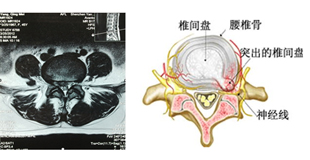

腰椎间盘突出症可以见于各个年龄段的成年人。腰椎间盘就像一个馅饼,馅心是髓核组织,饼皮是纤维环。椎间盘的纤维环是一个很坚韧的组织,但再坚韧的组织,也有受伤的时候。一旦出现扭伤,挫伤,没有得到正确的休息和治疗,就会导致创伤不断的加重,最后形成纤维环撕裂。随后,在体重的压迫下,馅心也就是髓核组织就慢慢脱离纤维环的限制,形成突出,压迫神经,导致腰腿疼痛。这就是腰椎间盘突出症。